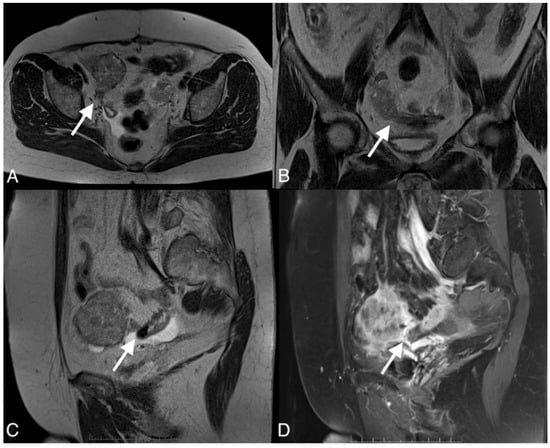

Figure 4.

Images of a 37-year-old woman with a recurrent tumor of high-grade serous ovarian cancer with fistula between tumor and sigmoid colon. MRI T2-weighted images obtained in axial plane (A), coronal plane (B), and T1 post-contrast (C) show a large solid/cystic tumor and the fistula (arrows) between tumor and sigmoid colon. DWI (b1200) shows restricted diffusion in the tumor but not in the fistula (D).

To confirm the suspected fistula, the patients were referred for MRI. In all cases, the fistula was visible on the MR images, showing hypointensity on the T2 and T1 post-contrast sequences but no restricted diffusion on the DWI sequence. The fistula in one of the patients was hyperintense on T2 images and hypointense on T1-weighted images and showed restricted diffusion on DWI.

The study showed that the DWI sequence was not superior to the other sequences in diagnosing fistulas on MRI, except for one of the patients in whom an acute inflammatory process was involved. Recent studies have shown that diffusion-weighted images are useful for diagnosing fistulas in the pelvis and determining whether they involve acute inflammation. However, DWI alone was not superior to T2 and T1 sequences with contrast [20]. DWI can show restricted diffusion in the tumor, which has an important role in the detection, characterization, and definition of local tumor spread [17].